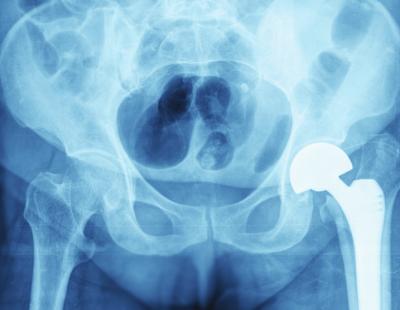

In the procedure, an arthritic or damaged joint is removed and replaced with an artificial joint called a “prosthesis.” Artificial joints are medical devices, which must be cleared or approved by the FDA before they can be marketed in the United States The goal of surgery is to relieve the pain in the joint caused by the damage done to cartilage, the tissue that serves as a protective cushion and allows smooth, low-friction movement of the joint. Total joint replacement is considered if other treatment options will not bring relief.

In an arthritic knee, the damaged ends of the bones and cartilage are replaced with metal and plastic surfaces that are shaped to restore knee function. In an arthritic hip, the damaged ball and socket of this joint are replaced by a metal ball and plastic socket. Several metals are usually used, including stainless steel, alloys of cobalt and chrome, and titanium. The plastic material is durable and wear-resistant polyethylene.